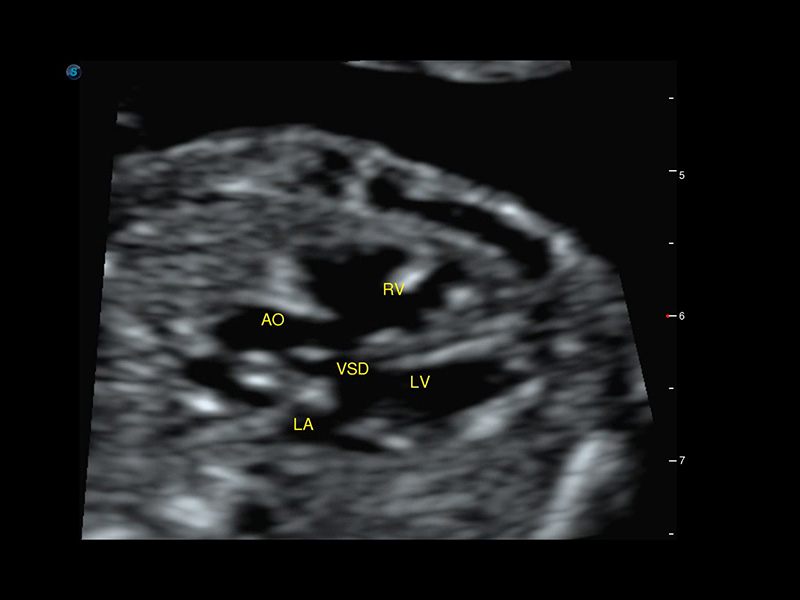

Bildgalerie